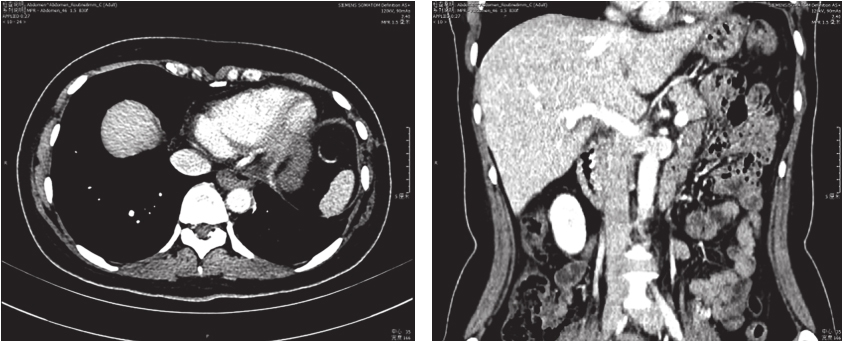

胸部及上腹部增强CT(图1):①左后下纵隔处见巨大不规则肿块影,横截面约13.4cm×12.3cm,考虑肿瘤性病变:胃肠间质瘤?②左侧胸腔、心包少量积液。③肝脏多发类圆形无强化低密度影,考虑囊肿。

图1 术前CT检查

肺部CT示(图4):食管术后改变,左膈膨隆升高,食管下段稍积气扩张,未见明显管壁及软组织密度影。胆囊、脾脏、胰腺及双肾未见明显异常。

图4 术后CT复查